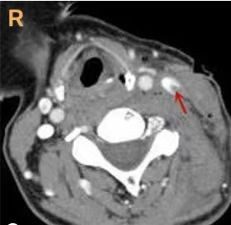

患者,女性,55岁。因“被犬咬伤左侧颈部致疼痛出血4 h”于2023-02-19 21:40送入本院抢救室,家属诉患者4 h前被犬咬伤颈部及左下肢,伤口疼痛伴大量出血,量约500 mL, 有头晕目眩,胸闷恶心,无呕吐。查体:体温36.4 ℃,呼吸频率20次/min,脉率72次/min,血压88/51 mmHg(1 mmHg=0.133 kPa),SaO2 95%。神志清,精神差,面色苍白,眼部及面部皮肤挫伤,左侧颈部4处伤口,最大处5 cm,余为2 cm、2 cm、1 cm(图 1),左小腿内侧12 cm皮肤撕裂伤,外侧4 cm、8 cm两处撕裂伤,均有活动性出血,肢体活动尚可。入院后予创口加压包扎止血。颈部增强CT示:左侧颈内静脉损伤(图 2)。诊断:(1)颈部开放性损伤;(2)失血性休克;(3)下肢开放性伤口。予以输注“去白红细胞2 U及冰冻血浆200 mL”,注射狂犬病免疫球蛋白等处置后建议急诊手术探查,家属知情同意后入手术室行颈部探查术+清创缝合术。术中见左颈4处伤口,最大处5 cm,余2 cm、2 cm、1 cm,延长大切口至7 cm左右予以探查,见左侧胸锁乳突肌部分断裂,分开肌肉见左颈内静脉局部裂口,边缘毛糙,长度约1 cm,裂口内血栓形成,取出血栓后见鲜血涌出,予血管破口缝合止血(图 3)。探查其余3处切口,左下切口较深,予以延长切口至3.5 cm左右,未见明显血管损伤,碘伏及生理盐水交替冲洗各伤口,两处较长伤口各放置引流片1条,颈部无菌敷料加压包扎伤口,左小腿创口清创缝合,全麻清醒后回耳鼻咽喉科病房。

| 图 2 术前颈部增强CT示左侧颈内静脉损伤 |